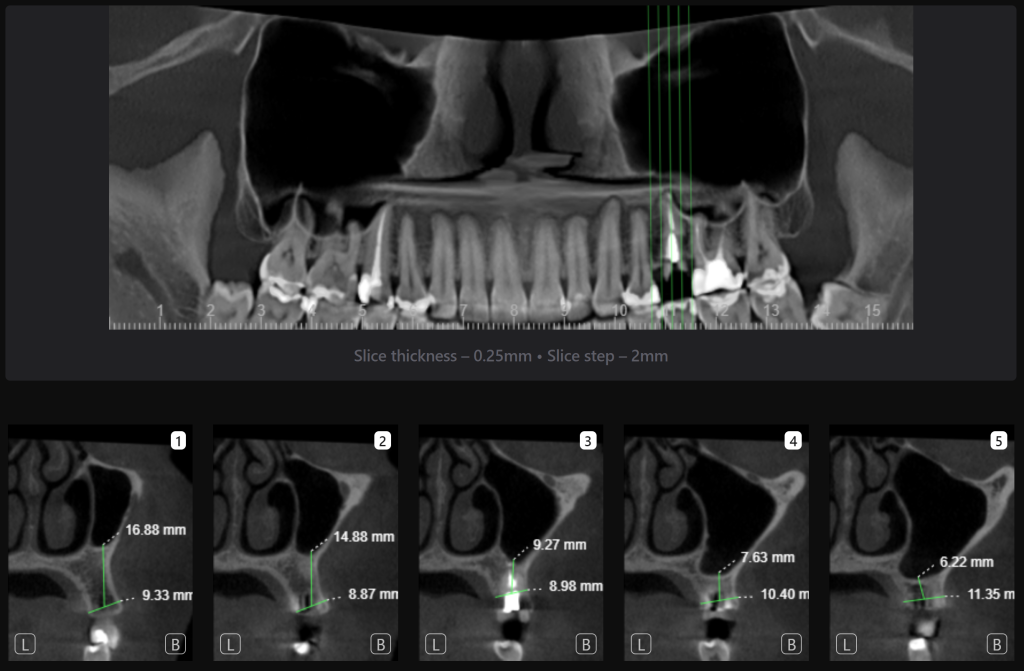

«Имплантологический отчет», созданный искусственным интеллектом Diagnocat, помогает определить оптимальные размер и расположение имплантата в соответствии с индивидуальными особенностями анатомии